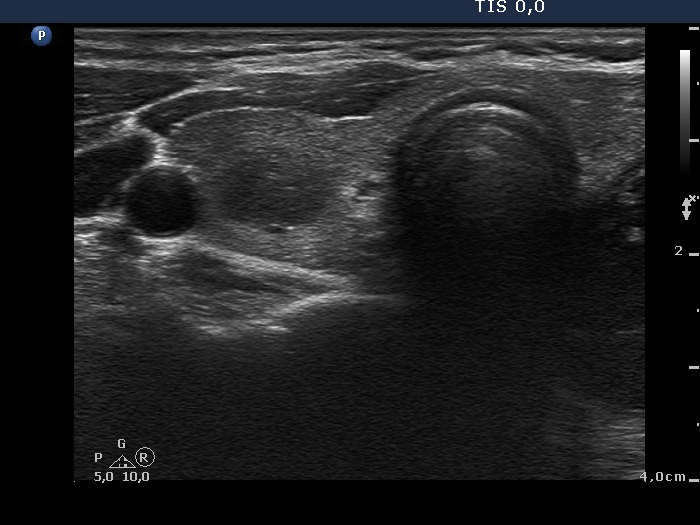

Study on 100 consecutive patients with thyroid nodule - case 057 (ultrasonographic picture 2)

Right lobe, another transverse scan. The nodule presents both hyperechogenic lines and granules, i.e. fibrotic changes.